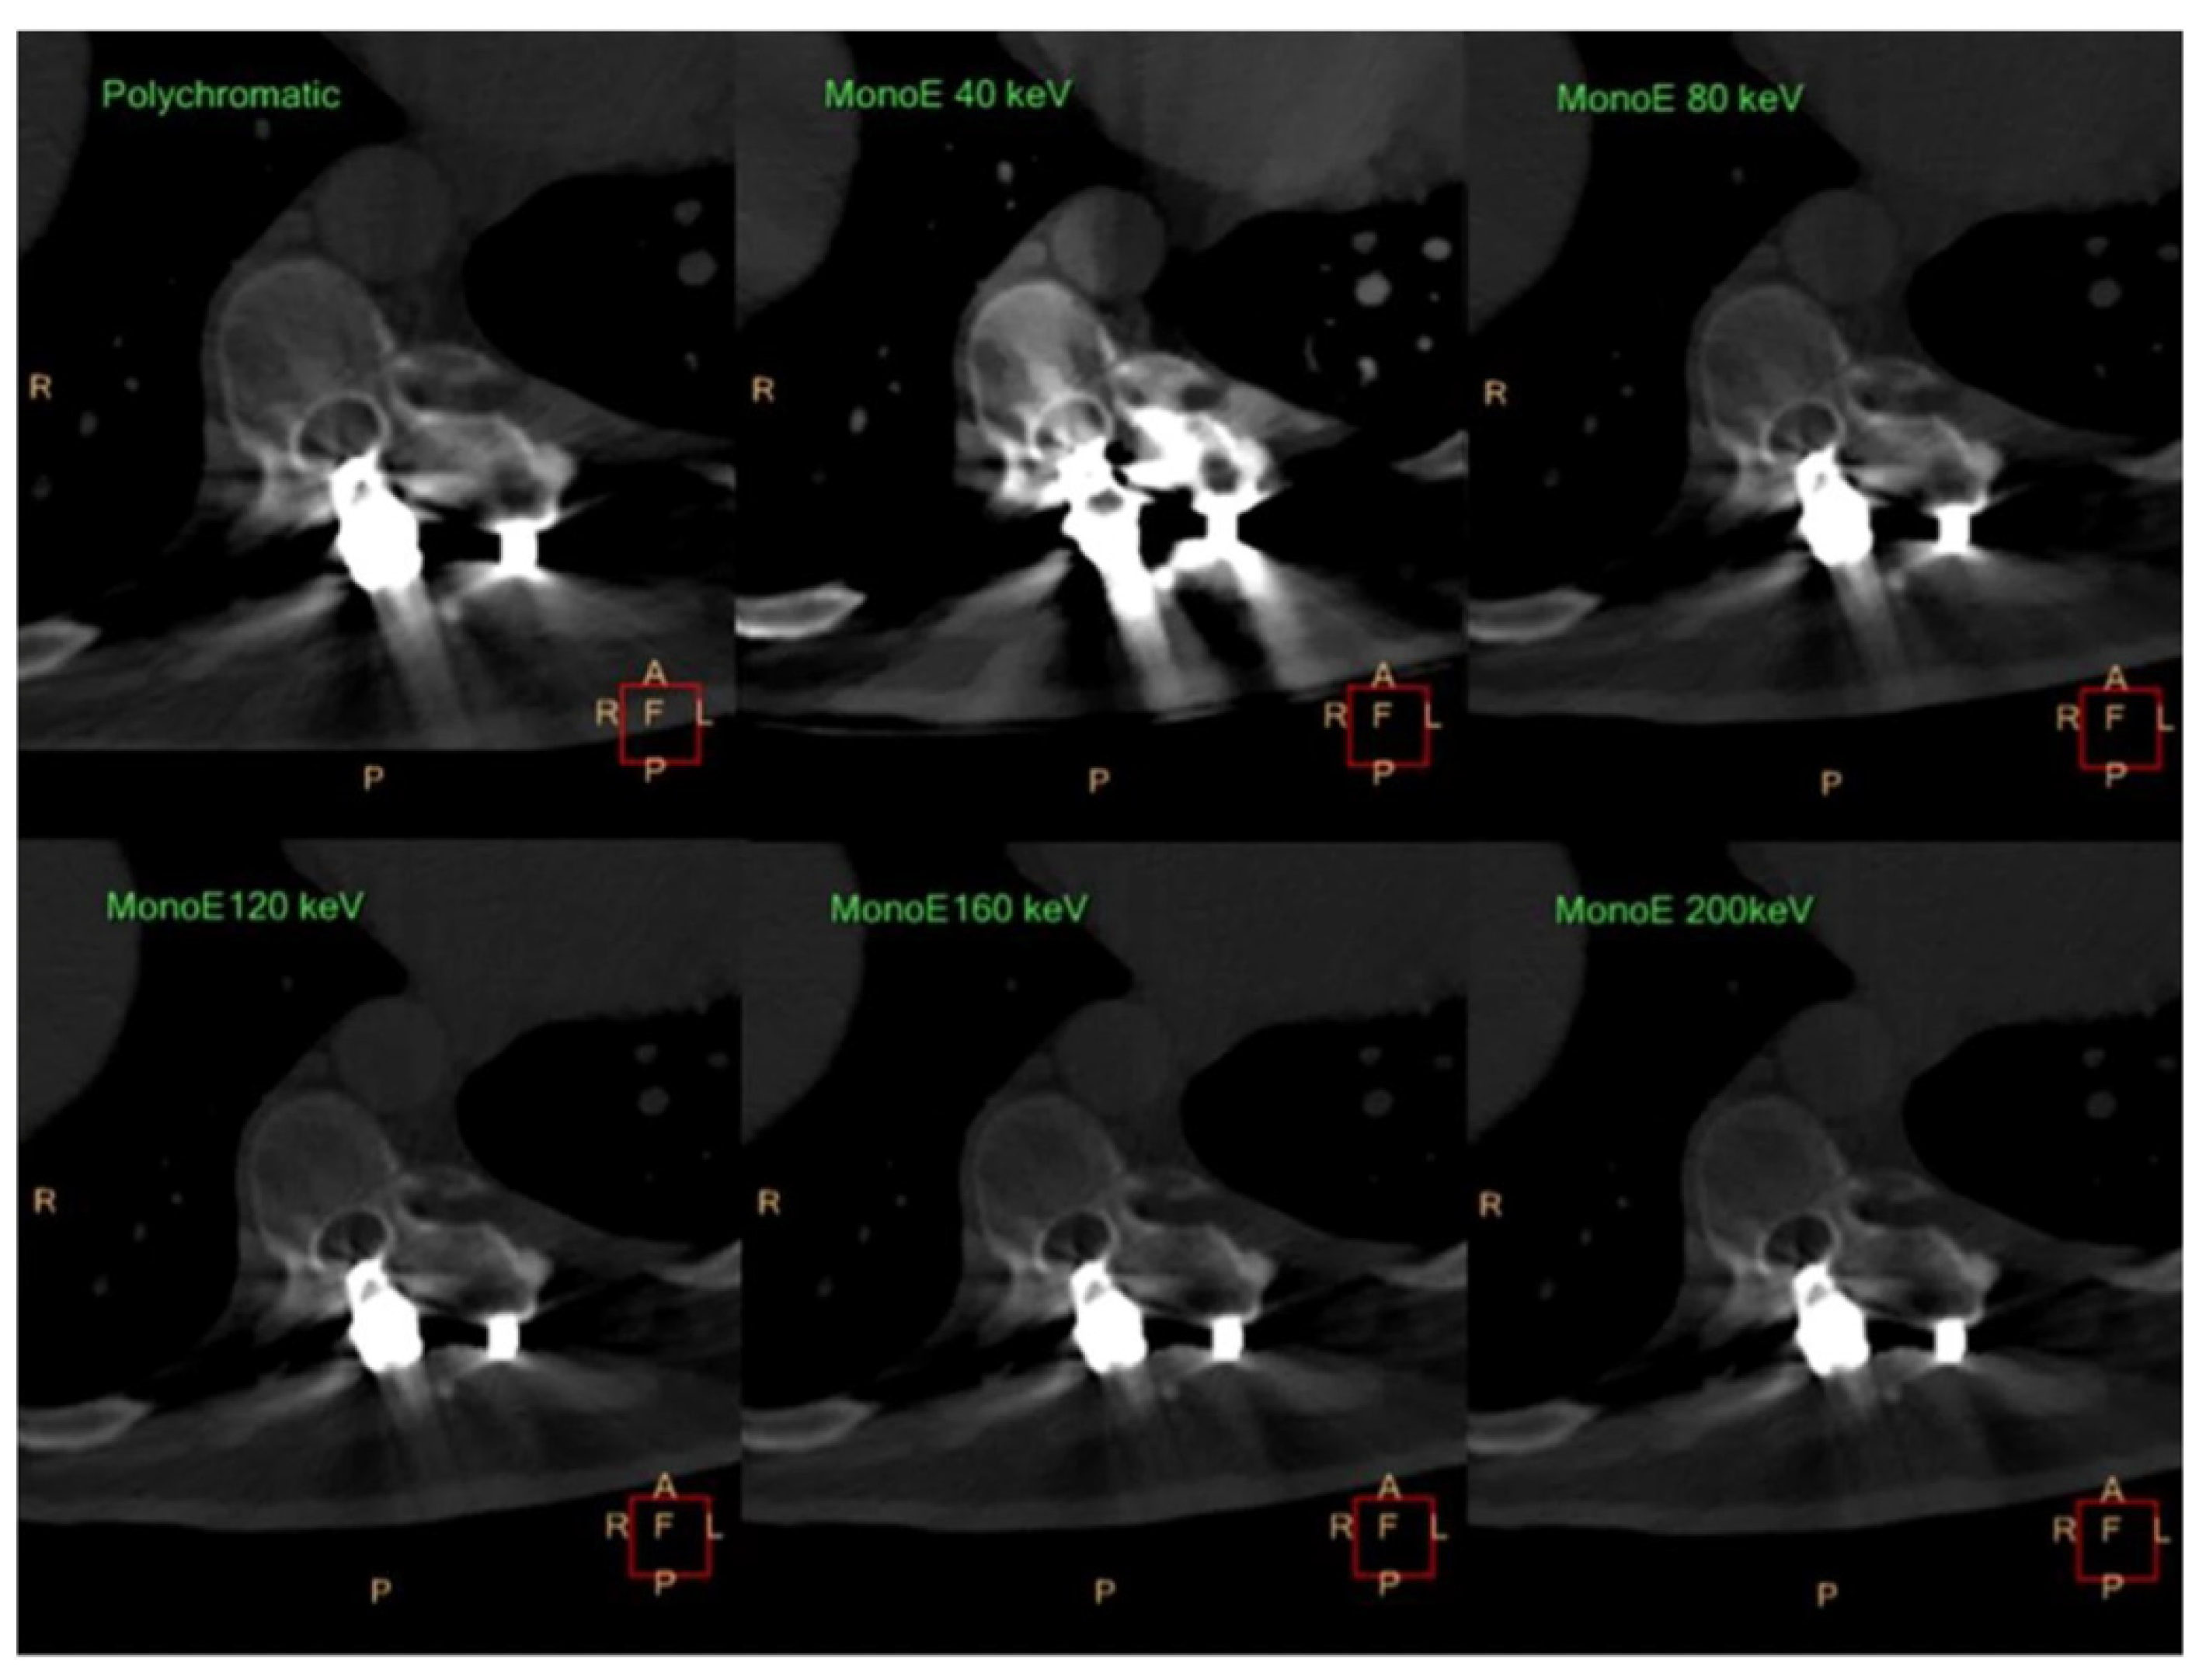

- Neuhaus, V.; Hokamp, N.G.; Abdullayev, N.; Rau, R.; Mpotsaris, A.; Maintz, D.; Borggrefe, J. Metal artifact reduction by dual-layer computed tomography using virtual monoenergetic images. Eur. J. Radiol. 2017, 93, 143–148. [Google Scholar] [CrossRef] [PubMed]

- Long, Z.; DeLone, D.R.; Kotsenas, A.L.; Lehman, V.T.; Nagelschneider, A.A.; Michalak, G.J.; Fletcher, J.G.; McCollough, C.H.; Yu, L. Clinical Assessment of Metal Artifact Reduction Methods in Dual-Energy CT Examinations of Instrumented Spines. AJR Am. J. Roentgenol. 2019, 212, 395–401. [Google Scholar] [CrossRef] [PubMed]